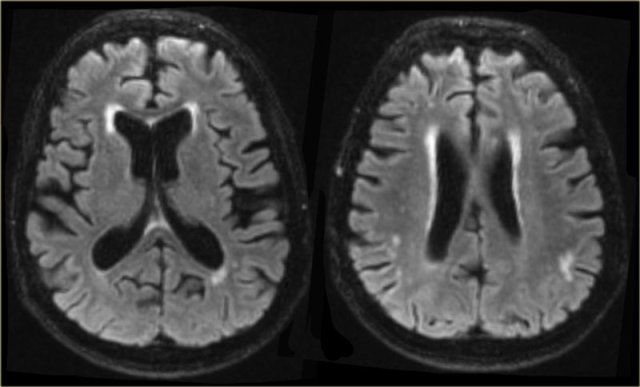

Imaging shows characteristic atrophy of the caudate nucleus and subsequent enlargement of the frontal horns of the lateral ventricles.

Cerebral Autosomal Dominant Arteriopathy with Subcortical Infarcts and Leukoencehalopathy (CADASIL)

CADASIL is another hereditary disease which may present with a progressive cognitive dysfunction.

Other presenting symptoms include migraines, stroke-like episodes and behavioral disturbances. It affects the small vessels of the brain.

Confluent white matter hyperintesities in the frontal and especially anterior temporal lobes in combination with (lacunar) infarcts and microbleeds are seen on imaging.

The FLAIR images show classic findings in CADASIL - confluent white matter hyperintensities with lacunar infarcts and involvement of the anterior temporal lobes.